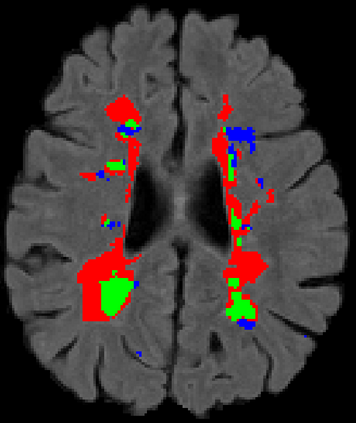

Recently, segmentation methods based on Convolutional Neural Networks (CNNs) showed promising performance in automatic Multiple Sclerosis (MS) lesions segmentation. These techniques have even outperformed human experts in controlled evaluation conditions such as Longitudinal MS Lesion Segmentation Challenge (ISBI Challenge). However state-of-the-art approaches trained to perform well on highly-controlled datasets fail to generalize on clinical data from unseen datasets. Instead of proposing another improvement of the segmentation accuracy, we propose a novel method robust to domain shift and performing well on unseen datasets, called DeepLesionBrain (DLB). This generalization property results from three main contributions. First, DLB is based on a large group of compact 3D CNNs. This spatially distributed strategy ensures a robust prediction despite the risk of generalization failure of some individual networks. Second, DLB includes a new image quality data augmentation to reduce dependency to training data specificity (e.g., acquisition protocol). Finally, to learn a more generalizable representation of MS lesions, we propose a hierarchical specialization learning (HSL). HSL is performed by pre-training a generic network over the whole brain, before using its weights as initialization to locally specialized networks. By this end, DLB learns both generic features extracted at global image level and specific features extracted at local image level. DLB generalization was validated in cross-dataset experiments on MSSEG'16, ISBI challenge, and in-house datasets. During experiments, DLB showed higher segmentation accuracy, better segmentation consistency and greater generalization performance compared to state-of-the-art methods. Therefore, DLB offers a robust framework well-suited for clinical practice.